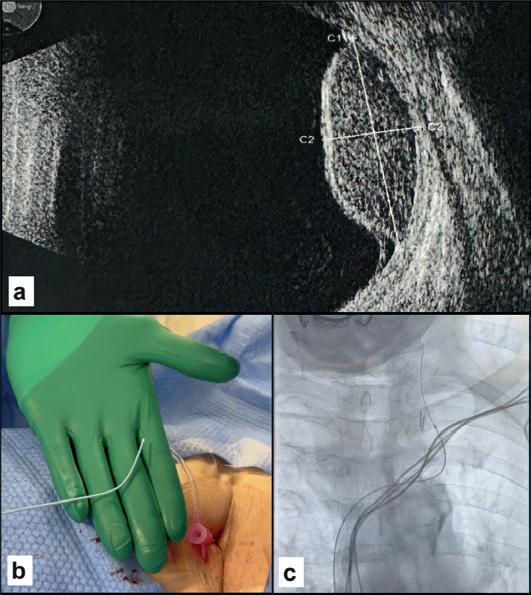

Male, 76 years old

Spiculated lung nodule, 14mm (A) in the right lower lobe, ischaemic heart disease, respiratory failure. Liquid biopsy from the right subclavian vein (B, C) with a finding of pathogenic mutation CDH1. Surgical histological confirmation of minimally invasive adenocarcinoma.

this biomarker. The simplest method, investigated by us and confirmed by another research group, is to draw venous blood in proximity to the tumour site. Percutaneous venous catheterisation is part of the armamentarium of interventional radiologists and relies on their familiarity with navigating the vascular system under fluoroscopic guidance. Sampling sites can be chosen as dictated by the natural history of the disease, which includes both primary and metastatic sites.

High-grade right frontal glioblastoma extending to the corpus callosum (A, B). Surgical histological confirmation but with negative tissue-based molecular testing. Pre-operative liquid biopsy from the right jugular vein (C) showing BRAF and PIK3CA mutations. Negative peripheral sample (D).

where venous sampling provides more effective molecular characterisation than peripheral sampling.